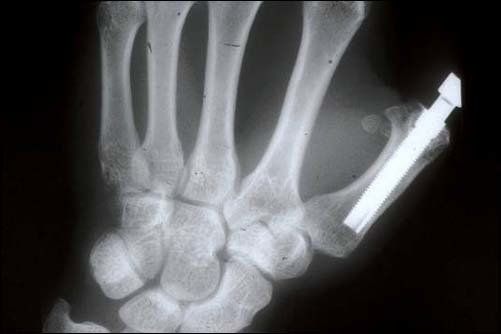

È necessario effettuare una visita che consentirà, in seguito a radiografie, calchi in gesso e fotografie, di effettuare nel dettaglio un’analisi preliminare del singolo paziente.

Coloro che hanno perso uno o più denti a causa di traumi, malattie o a seguito della loro semplice caduta, rappresentano dei candidati ideali per gli impianti e le protesi dentali. Il principale limite all'installazione di tali impianti è rappresentato dalla quantità di osso disponibile: per questo motivo, il dentista Calandriello, esperto di implantologia a Bologna, è la persona più indicata per valutare le soluzioni perseguibili.